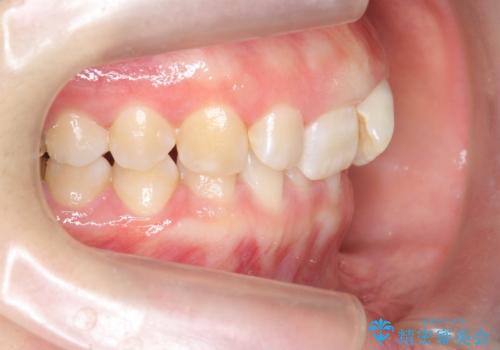

ねじれた前歯を改善するマウスピース矯正

- 大きくねじれた前歯をまっすぐに並べたい。と矯正治療を希望され来院されました。

前歯をきっちり並べるには奥歯の噛み合わせの調整を行い上下の前後的関係を治し、ねじれを取るスペースを確保していきます。

当初前歯だけ治れば良い、という心算で来院されましたが奥歯の噛み合わせも負担が大きく問題の起きやすいことをお伝えし上顎の奥歯をきっちりと後方移動行い噛み合わせの調整を行いました。・